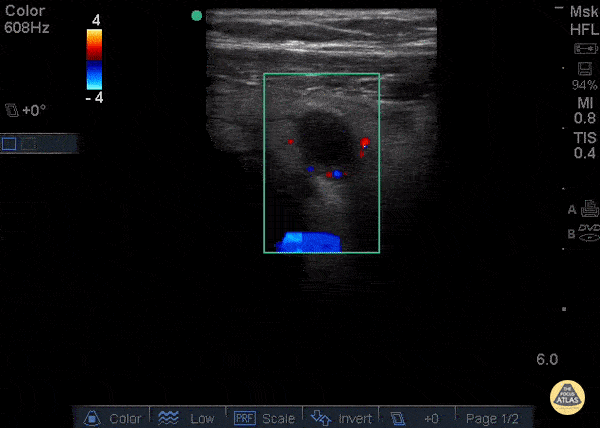

12 y/o with appendicitis. Using color-flow doppler, you can see increased vascularity surrounding the appendix, referred to as a “Ring of Fire” Dr. Sathya Subramaniam